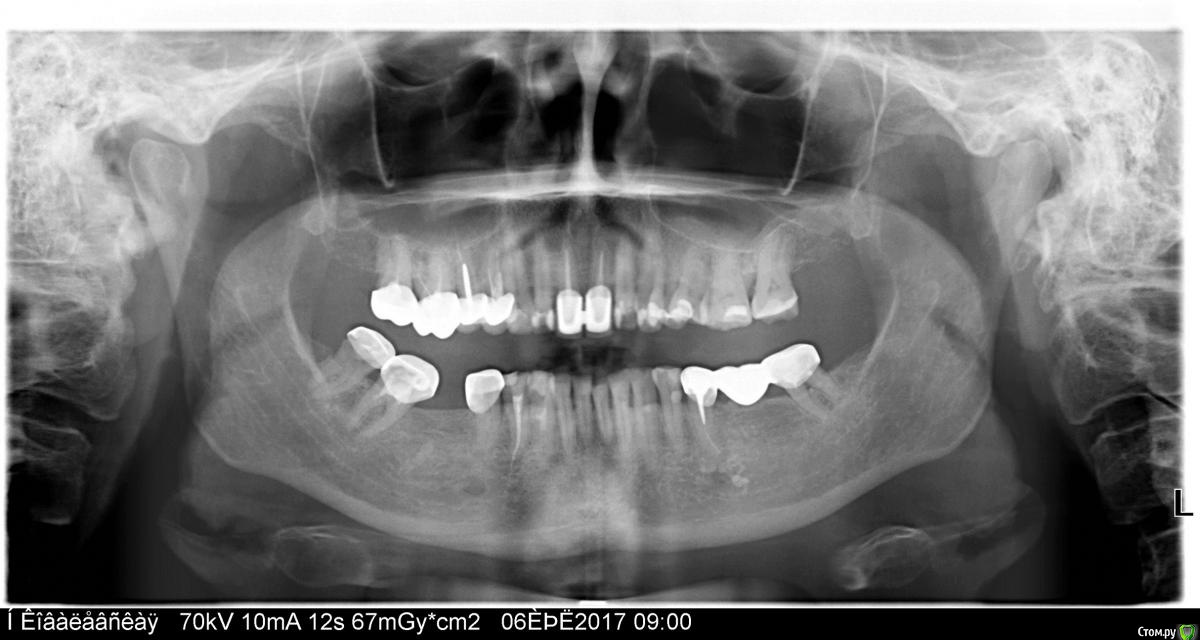

Зуб болит Опубликовано 23 июля, 2017 Поделиться Опубликовано 23 июля, 2017 После уколов гиалуроновой кислоты в лицо, неожиданно появилась боль при накусывании в районе верхних левых четвёрки-пятерки. Поднывала вся челюсть после этого. Обратилась к стоматологу. Он убил нерв в левой верхней четвёрке. Прошло уже больше двух недель после этого. Ничего не изменилось. Боль такая-же пронизывающая. Кажется, что пятёрка. Подскажите пожалуйста, проблема с пятым зубом? Или неврологическая проблема и лечение четверки было ошибочным? Ссылка на комментарий

Зуб болит Опубликовано 24 июля, 2017 Автор Поделиться Опубликовано 24 июля, 2017 когда сделан этот снимок? Покажите снимки зуба до, и после леченияСнимок сделан перед лечением две недели назад. После пломбировки канала снимок не делали Ссылка на комментарий